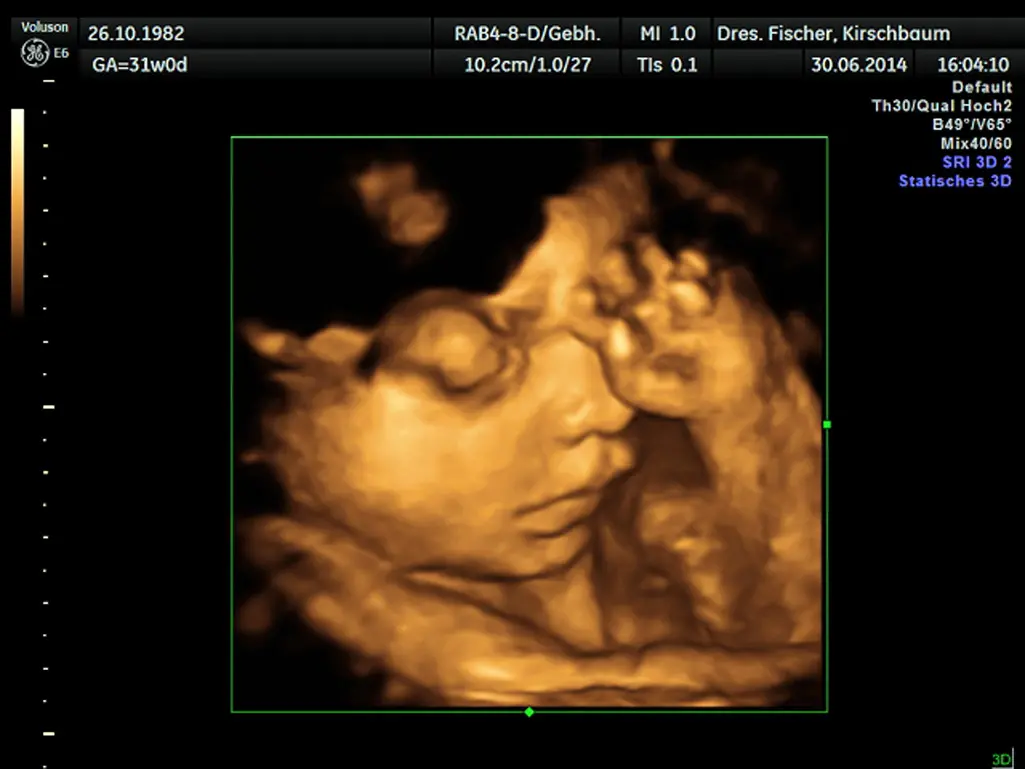

- Screening: In der 1bis 2Schwangerschaftswoche. Dieses Screening dient dazu, die Entwicklung des Kindes zu überprüfen, mögliche Fehlbildungen zu erkennen und die Lage der Plazenta zu beurteilen.

- Screening: In der 2bis 3Schwangerschaftswoche. Dieses Screening dient dazu, die Entwicklung des Kindes weiter zu beobachten, die Menge des Fruchtwassers zu überprüfen und die Lage des Kindes im Mutterleib zu beurteilen.